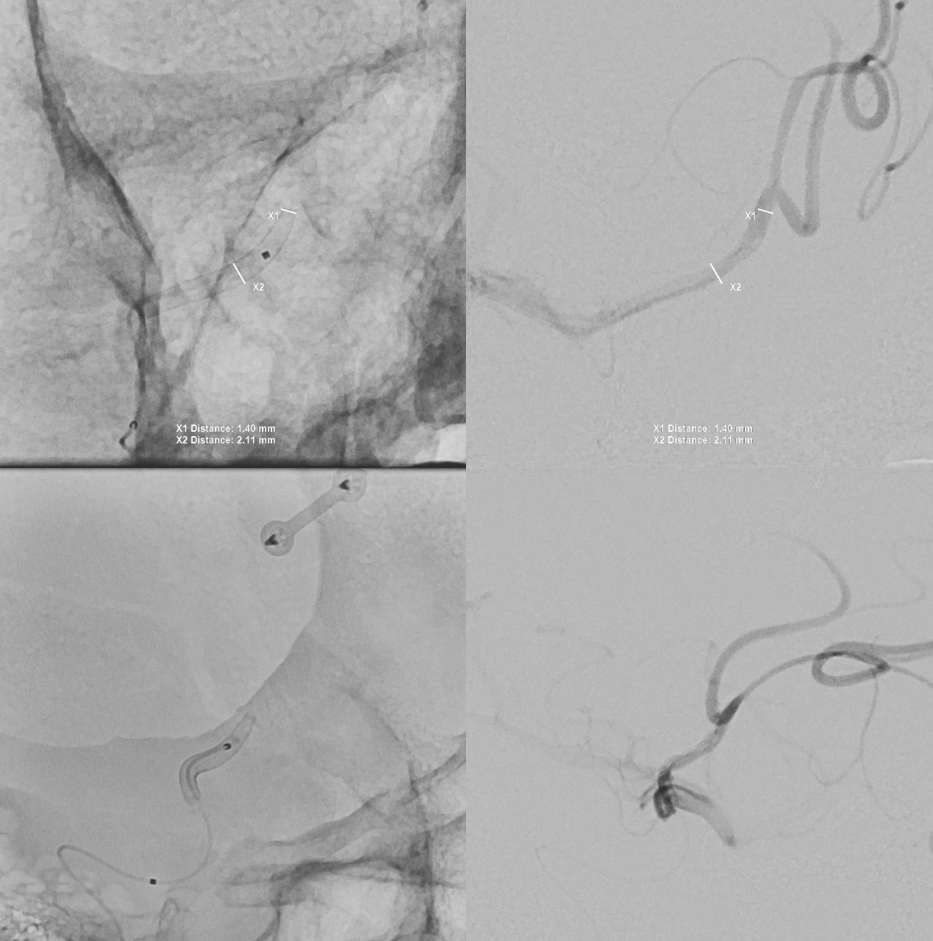

Aristotle 14 soft and Scepter C 4×10

Now we do a BTO of the right A2. Its not a perfect occlusion there is a small endoleak. Still, the brisk filling of right A2 suggests what?

The first SVB is deployed. However, there is a concern. What is it? Look at the measurements of the SVB and the landing zones

The answer is possible endoleak. The distal landing zone may be too short for a nitinol device. The diameter of the proximal SVB is smaller than the expected diameter of the A2 target. Its a critical point. If this is missed, the treatment may fail

The answer is to either balloon it or put in another device. We put in another SBV, now extending it into one of the A2 branches. Yes, one can argue that with working bypass you can just close the A1-A2 junction. Sure. But we did not know this before. And we can always do that later by coiling inside the SVB. Here, we keep options open.

Post SVB 2

Look at the difference in measurements after SBV 2 (top row) and SBV 1 (bottom row). Arrows point to location of the SVB 1 distal landing zone